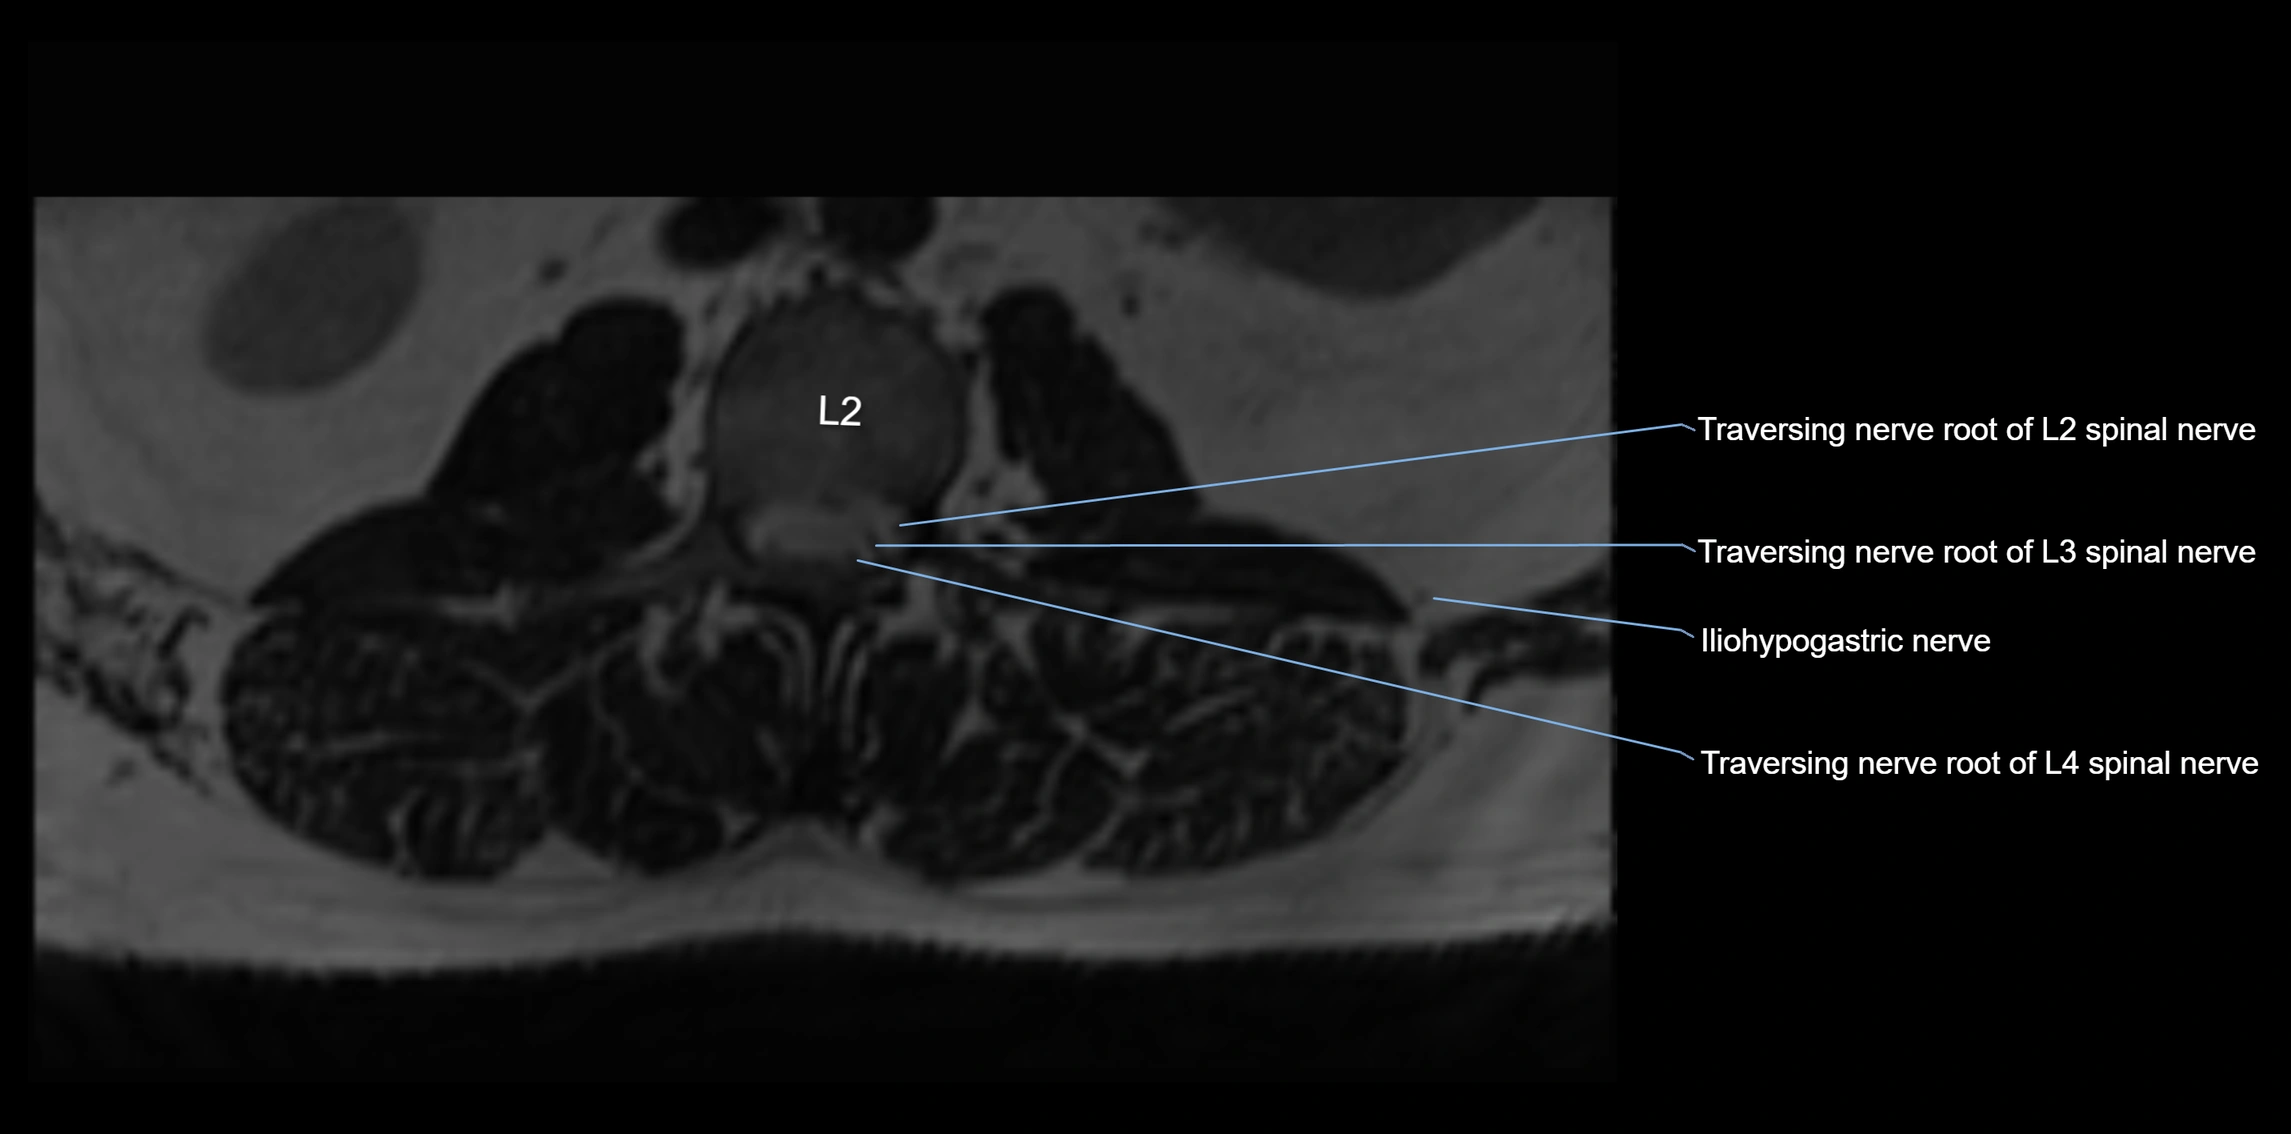

MRI image

image